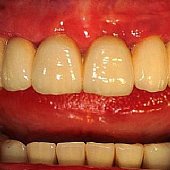

Bilder: Gesamtsanierung

• Die fertige Versorgung - mit stark individualisierten Zähnen kann man ein möglichst natürliches Ergebnis erzielen.

• Die eingegliederte Vollkeramikbrücke.